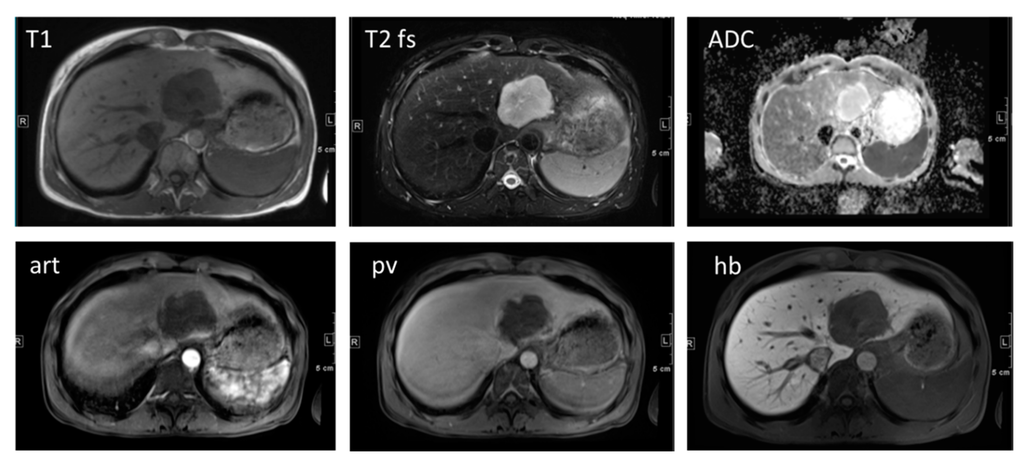

3. Magnetic Resonance Imaging (MRI)

3.1. Hepatocyte Specific MRI Contrast Agents

3.2. Diffusion-Weighted MR Imaging

3.3. Dynamic Contrast Enhanced MRI